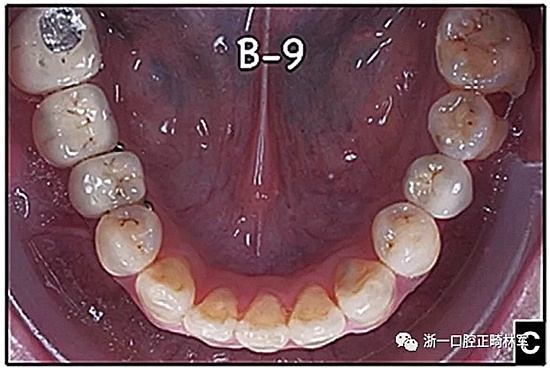

圖15.A,去除固定裝置一個(gè)月后,下頜左側(cè)第二前磨牙復(fù)發(fā),移動(dòng)到種植體愈合的部位; B,B-0表示開(kāi)始再治療,通過(guò)鏈圈和推簧的矯正復(fù)發(fā); C,B-9是治療結(jié)束后3個(gè)月回訪(fǎng)時(shí)下頜弓的咬合面觀(guān),這是再治療階段的9個(gè)月。下頜左側(cè)第二前磨牙和第三磨牙的頰面粘合一個(gè)固定保持器,以防止復(fù)發(fā)。